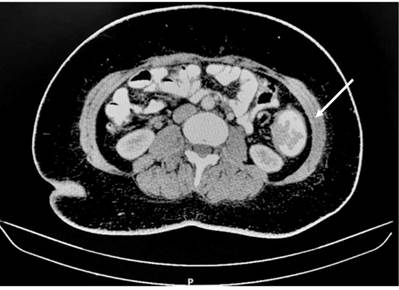

Se realizaron estudios de extensión y estadificación, dentro de ellos un antígeno carcinoembrionario cuantificado en 1,35 ng/mL, tomografía axial computarizada (TAC) de abdomen con contraste que mostró una masa polipoide dependiente del colon descendente de aproximadamente 45 mm de diámetro, irregular, ulcerada, asociada con estriación de la grasa perilesional y adenopatías en el borde mesentérico; además, se observó el hígado con una lesión focal en el segmento VII de 98 mm y el segmento IV de aproximadamente 10 mm (Figura 1). Se realizó una resonancia magnética (RM) de abdomen que evidenció lesiones focales en el segmento hepático IV de 7 mm y el lóbulo derecho de 7,4 mm, que en el contexto sugieren metástasis hepáticas (Figura 2).

Figura 1 TAC de abdomen con contraste realizado durante la admisión en el que se muestra un tumor dependiente del colon sigmoides con gran compromiso de la luz intestinal.